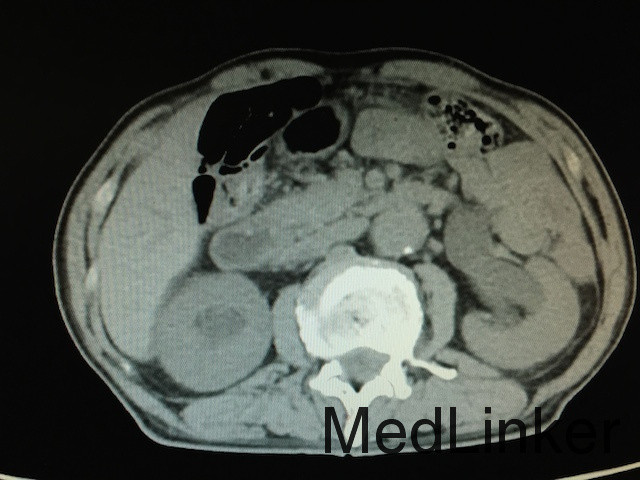

查体:无明显异常。 辅助检查:泌尿系CT(如下图所示):膀胱实性占位,增强扫描肿物呈不均匀强化,双侧输尿管及肾盂积水,结合患者既往史,考虑膀胱恶性肿瘤复发;骨扫描未提示骨转移灶;胸片无明显异常。

诊断:膀胱恶性肿瘤复发、双肾积水、膀胱憩室 治疗:建议行膀胱癌根治术+尿路转流术,患者家属拒绝,故行膀胱镜探查及双侧输尿管支架植入术改善双肾积水,改善肾功能。